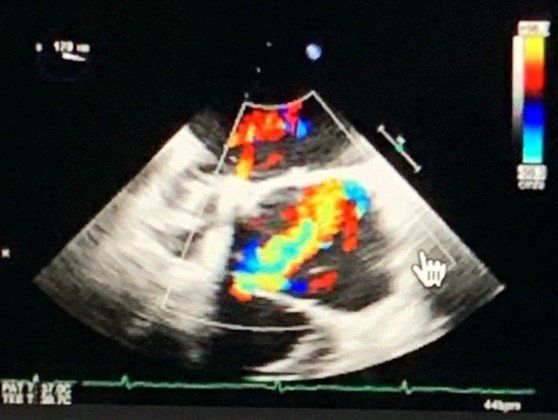

The first type is the Transthoracic Echocardiogram (TTE). This is performed while lying flat on your back. There's a machine with a screen and a handheld probe.

The technician will rub ultrasound gel on your chest and run the probe around your chest picking up sound waves from your heart.

Images will appear on the screen that will show the technician the structure of your heart valves along with the strength that your heart Is pumping. This test runs for 15-20 minutes.